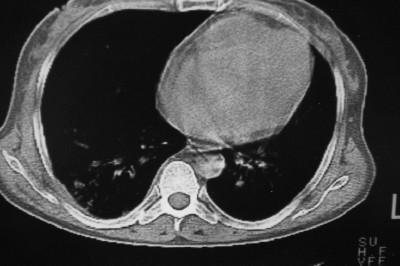

以下是引用天南地北在2007-4-10 1:49:00的发言:[br]考虑右下叶周围型肺癌伴肋骨转移。

以下是引用jone-baby在2007-4-10 8:45:00的发言:[br][br] [br] 患者[br]有发热史,x线片考虑肺脓肿.肺脓肿可以导致肋骨破坏吗?[br]脓肿可以排除吗? [br] [br] [br]

以下是引用林建春在2007-4-10 7:35:00的发言:[br]周围型肺癌侵犯肋骨

以下是引用liuyue在2007-4-10 7:56:00的发言:[br]周围型肺癌侵犯肋骨,左肺转移。

以下是引用zhangzhongshou在2007-4-10 10:24:00的发言:[br]右肺下叶背段厚壁空洞,伴胸膜改变、肋骨破坏,其内可见死骨、周围骨质硬化,左肺可见小结节影,[br]单纯影像学更支持结核。建议进一步检查。